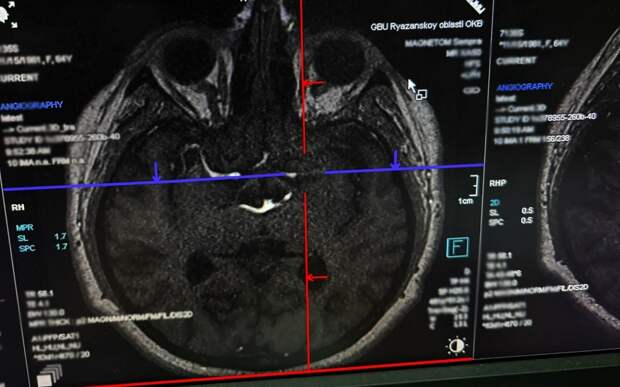

Рязанца госпитализировали, подтвердился инсульт. Больше двух недель мужчина провел в больнице.